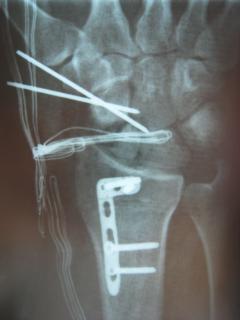

Διεγχειρητικά

Περίπτωση 2: Μετεγχειρητικά 1